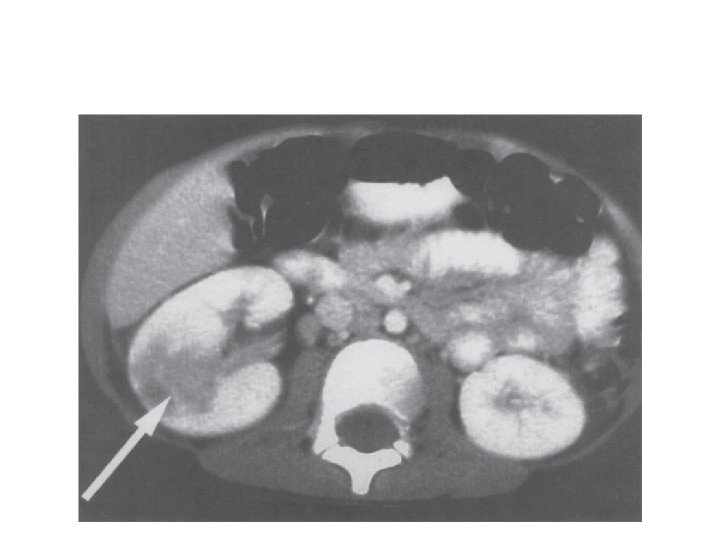

Pyonephrosis. Ultrasonography demonstrates fluid–debris level (white arrow) within the dilated renal pelvis.